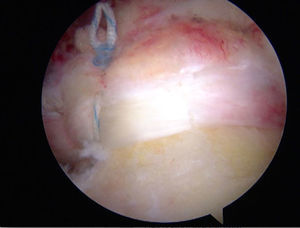

En la técnica de fila sencilla o una sola fila se colocan anclajes de 5,0 o 5,5 mm (titanio biodegradable o peek) en el margen lateral de la tuberosidad mayor, se pasan los puntos a través del tendón aproximadamente a 15 mm en sentido medial al borde de la rotura. Se utiliza el número de anclajes de acuerdo con el tamaño de la rotura. También se debe tener en cuenta con cuántas suturas está cargado el anclaje. En la mayoría de diseños tiene dos suturas reforzadas. Para las roturas en forma creciente se puede realizar la reparación con puntos sencillos, pero, cuando son lesiones de mayor extensión o en forma en L, se recomienda combinar puntos de borde a borde y fijación con anclajes (figs. 14–16).

En la técnica de doble fila se colocan uno o dos anclajes mediales en el borde articular de la cabeza humeral, se pasan puntos sencillos a través del tendón y se anudan las dos suturas de cada anclaje con nudos deslizantes bloqueados. Los anclajes laterales se colocan en el borde lateral de la tuberosidad mayor y se anudan con las suturas mediales, ya sea con nudos deslizantes bloqueados o con los sistemas de no nudos existentes en el mercado. Una de las principales complicaciones en la reparación del manguito de los rotadores es la rerrotura, pero es muy importante tener en cuenta que en muchas ocasiones no existe una correlación directa entre una rerrotura, ya sea parcial o completa, con los resultados clínicos y funcionales44. Sin embargo, existe una relación directa entre la cicatrización y la fuerza postoperatoria (figs. 17–19).